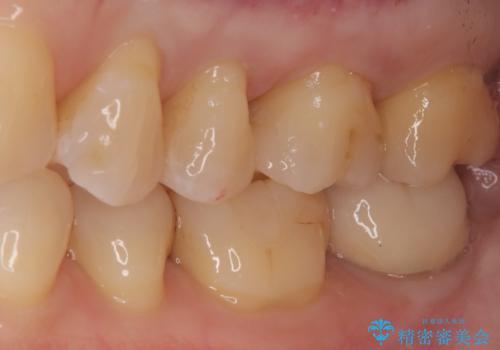

治療では、まず古い金属のインレーを慎重に取り外しました。金属の下に隠れていた虫歯の再発がないかを確認し、歯を丁寧に形成。その後、精密な型取りから患者様の歯の色に合わせたオーダーメイドのセラミックインレーを作製しました。セラミックは、自然な光の透過性を持つため、周囲の歯と区別がつかないほどの美しい仕上がりとなります。適合性の高いセラミックインレーを装着することで、再発のリスクを抑えつつ、長年のコンプレックスだった銀歯がなくなり、笑顔でも気にならない自然な奥歯を取り戻していただけました。